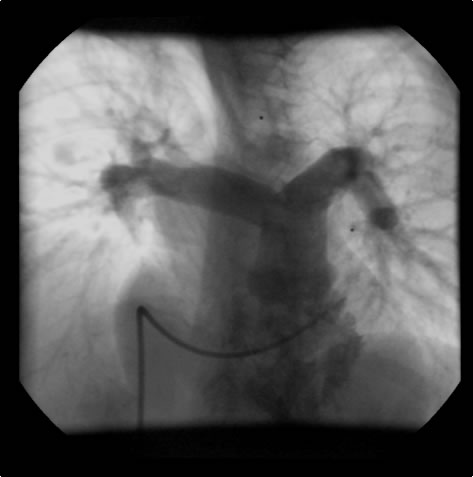

Figure 2: Preoperative cardiac catheterization. Figure 3:The "waist" in the ascending aorta is readily apparent. The "waist" is above coronary orifices. Figure 4: AP/Lateral ventriculogram. The patien has no subaortic obstruction. Figure 5: Main pulmonary artery injection. There is no peripheral pulmonary artery stenosis.